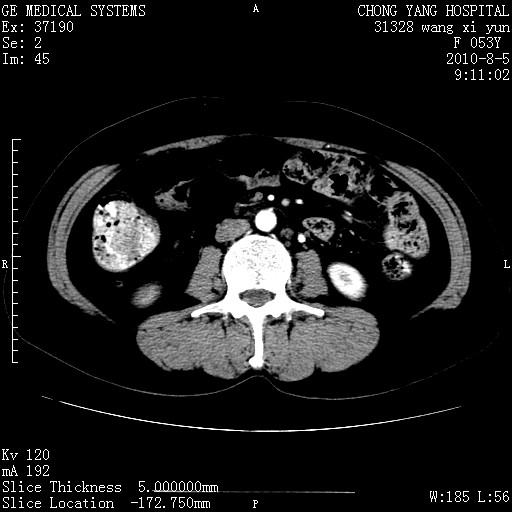

标题: CT28214:F41Y 血尿二十天,建议盆腔平扫加增强。

1)考虑肝左叶胆管细胞癌。2)脂肪肝。